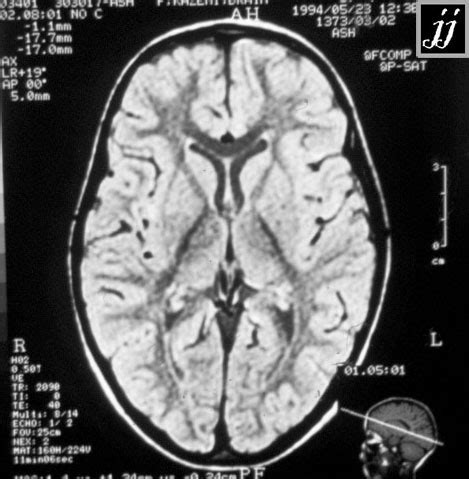

Alright guys, imagine you need to describe the location of something in your body. How do you do it precisely? That’s where anatomical planes and directional terms come in, and they are super important for understanding anatomy. Think of them as a universal language that scientists and doctors use. The first major plane is the sagittal plane . This plane divides the body vertically into right and left parts. If you draw a line straight down the middle of your nose and continue it down your body, that’s the median or midsagittal plane. Any plane parallel to this is a parasagittal plane. Then we have the frontal (or coronal) plane . This one divides the body vertically into anterior (front) and posterior (back) parts. Think of a crown worn on the forehead – that’s the coronal plane. Lastly, there’s the transverse (or horizontal) plane . This one divides the body horizontally into superior (upper) and inferior (lower) parts. This is like slicing a loaf of bread. Understanding these planes helps us visualize how structures are related to each other in three dimensions. Now, let’s talk directions. We use terms like anterior (front) and posterior (back) – basically front and back. Superior (towards the head) and inferior (towards the feet) refer to up and down. Medial means towards the midline of the body, while lateral means away from the midline. Think of your arms being lateral to your chest. Proximal and distal are used for limbs, with proximal meaning closer to the point of attachment or origin (like your shoulder is proximal to your elbow), and distal meaning further away (your fingers are distal to your wrist). We also have superficial (towards the surface) and deep (away from the surface). So, your skin is superficial to your muscles. Mastering these terms might seem a bit like learning a new language at first, but they are absolutely crucial for accurately describing and understanding anatomical locations and relationships. They remove ambiguity and ensure everyone is on the same page when discussing the human body. So, next time you hear about a structure being ‘anterior’ or ‘medial’, you’ll know exactly what that means!